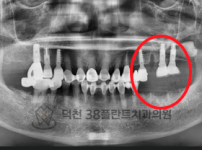

치료전후